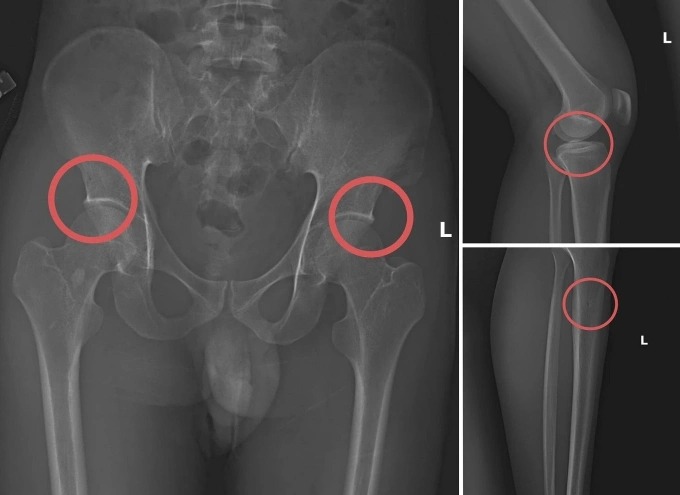

Các vết thương do ông Châu tự tạo nên. (Ảnh từ cơ quan điều tra)

Ông Châu trực tiếp thực hiện hành vi tiêm thuốc mê cho người mua bảo hiểm. Sau đó, dùng kim tiêm, búa, đinh để tác động vào xương. Hành vi này tạo nên các vết nứt, vỡ xương tương tự tai nạn thật.

Theo Thiếu tướng Nguyễn Minh Tuấn, Giám đốc Công an tỉnh Phú Thọ, thủ đoạn này vừa tàn nhẫn, vô nhân tính, vừa coi thường sức khỏe, tính mạng của người tham gia. Các đối tượng đã tính toán kỹ để gây thương tích đúng vị trí có mức chi trả cao. Điều này khiến các công ty bảo hiểm khó phát hiện dấu hiệu gian dối.